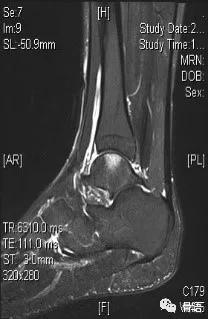

图2 患者术前MR矢状位片

图1、图2示术前ATFL连续性中断、显影模糊,提示ATFL撕裂,距骨软骨损伤,骨髓水肿。图3、图4示ATFL关节镜下带线锚钉固定联合PRP治疗术后6个月ATFL完整性存在,张力好,骨髓水肿信号较前减轻。该患者术后随访效果满意,症状较前明显减轻。